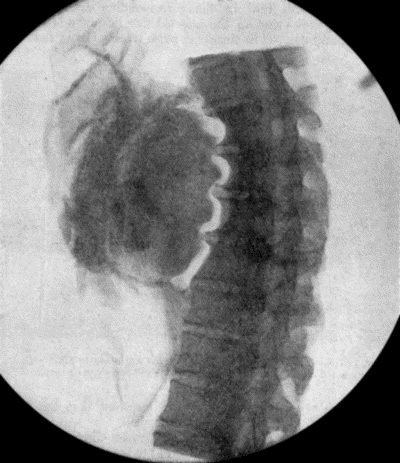

71.Radiogram of Aneurysm of Aorta 303

72.Sacculated Aneurysm of Abdominal Aorta 304

73.Radiogram of Innominate Aneurysm after Treatment by Moore-Corradi method 309

74.Thoracic Aneurysm threatening to rupture 313